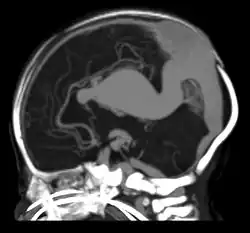

Maximum-intensity projection from a CT cerebral angiogram showing an aneurysmal deep venous structure which drains to the vein of Galen, and then to an abnormally dilated falcine sinus

A falcine sinus is a venous channel that lies within the falx cerebri connecting the vein of Galen and the posterior part of superior sagittal sinus.[1] It is normally present during fetal development and involutes after birth. The presence of a falcine sinus has been associated with a vein of Galen malformation and other vascular anomalies. The persistence of a falcine sinus after the neonatal period was previously thought to be rare, but has recently been described to be present in up to 5% of all people,[2][1] appearings in approximately 2.1% of CT examinations of adult patients. Some authors have studied the plexus rather than the sinus, a rare form of the venous pathway between the layers of the cerebral falx, which connects the superior sagittal sinus with the inferior sagittal sinus and the straight sinus.[3]